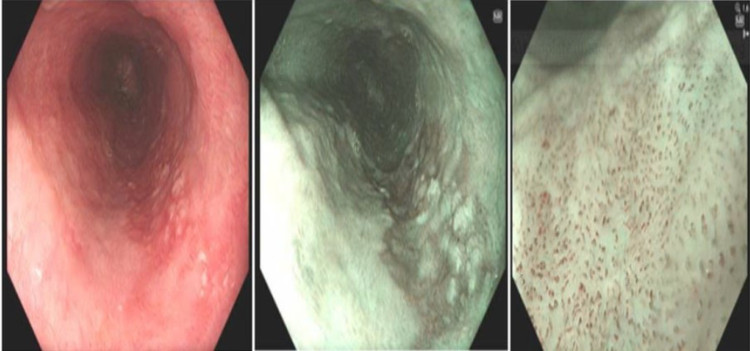

Hình ảnh tổn thương ung thư sớm thực quản trên nội soi.

Kết quả nội soi phát hiện tại thực quản cách cung răng trên từ 30cm đến 36cm có tổn thương thay đổi màu sắc kích thước khoảng 2cm x 5.5cm.

Dưới phân tích của kỹ thuật nội soi phóng đại và nhuộm màu ảo (NBI) tổn thương có đặc điểm vi cấu trúc mạch máu biến đổi phù hợp với một tổn thương ung thư sớm. Các bác sĩ đã tiến hành sinh thiết tổn thương gửi làm giải phẫu bệnh, kết quả loạn sản độ cao.